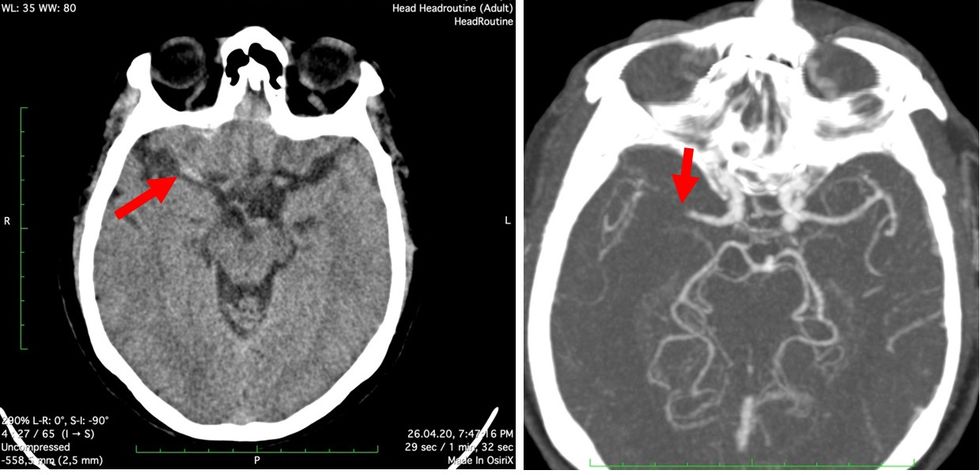

Me imazheri me TK dhe ADS konfirmohet mbyllja e arteries trunore të mesme djathtas.

Me mundësitë me materiale në dispozicion kemi arritur të rekanalizojmë vetëm degën e poshtme të ACM djathtas.

Në kënaqësinë e gjithë ekipit, pacienti akoma në tavolinën e angjiografisë ka rikthyer funksionin e humbur.

Pacienti akoma në tavolinën e angiografisë, menjëherë pas rekanalizimit të ACM djathtas ka rikthyer funksionin e dorës së majtë